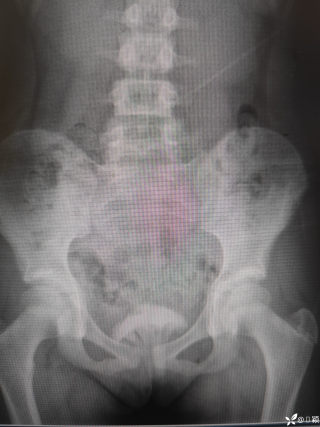

西地兰vip普外科医师

文/西地兰 特别声明:所有观点仅代表个人言论 特别声明:与当事双方均无利益相关 山东男孩,目前全网沸沸扬扬,看过一些观点,直言不讳地说,大多偏颇。要么一股脑地指责医方的全责,甚至有说千万别在县医院看病。要么又为医方无休止的遮羞,认为这样的手术在县医院做下来已经非常了不起。而我想到的是,以后面临类似的病例,我们怎么办?那么我们不如来一次专业的病案讨论。既然是事后讨论,难免有事后诸葛亮的感觉,但是假如下一次,同行们遭遇这样的病例,如何处置?这是医疗行业所面临的问题。希望我整理的这些思路和相关病例,对同行们有所帮助!就目前的资讯外界不足以判断是否需要急诊,如果需要急诊,那么只能根据术中所见进行处理,

目前知道的消息,第一,术前发现一个血肿,然后做增强CT发现一个占位,没说血肿与肿瘤的关系,术后病理没有描述肿瘤出现破裂出血,大概率就一个小血肿,我就不明白当地主任凭哪个指针去给这小孩开急诊刀的?哪个指南告诉他需要急诊开?第二,诊断不明确他想的不是进一步检查,一边观察一边进一步查,他反而选择腹腔镜探查,这个探查的指针在哪?第三,腹腔一个血肿,没有活动性出血,没有血压心率出现问题,为什么要开腹进去碰它?不能等血肿吸收再明确肿瘤性质吗?第四,1点进腹,3点病理结果出来,按这个时间还算顺利,应该还没出事,孩子还算平稳,病理是低度恶性,切了就治愈,他一年能开几台这手术,就敢继续做,拿孩子练手。第五,后面

2023年10月26日,来自山东菏泽市成武县的小烨和他家人的命运被彻底改变了。这个原本阳光、可爱的小男孩在一次意外被撞击后,在医院检查出了腹腔内存在肿瘤,并在手术中被切除了包括十二指肠、胰腺、大部分胃和小肠等多个器官。此后便无法再像正常人一样吃饭、喝水,活着要靠长期静脉注射营养液。一份2024年12月由第三方机构出具的司法鉴定意见书显示,当时给小烨做手术的成武县人民医院在该医疗行为中存在过错,与小烨的损害后果之间存在因果关系,建议医疗过错在损害后果中的原因力大小为同等原因。此外,另一份由成武县卫生健康局在2025年9月28日发出的书面答复中显示,成武县人民医院存在24小时内未完成病历;手术知情